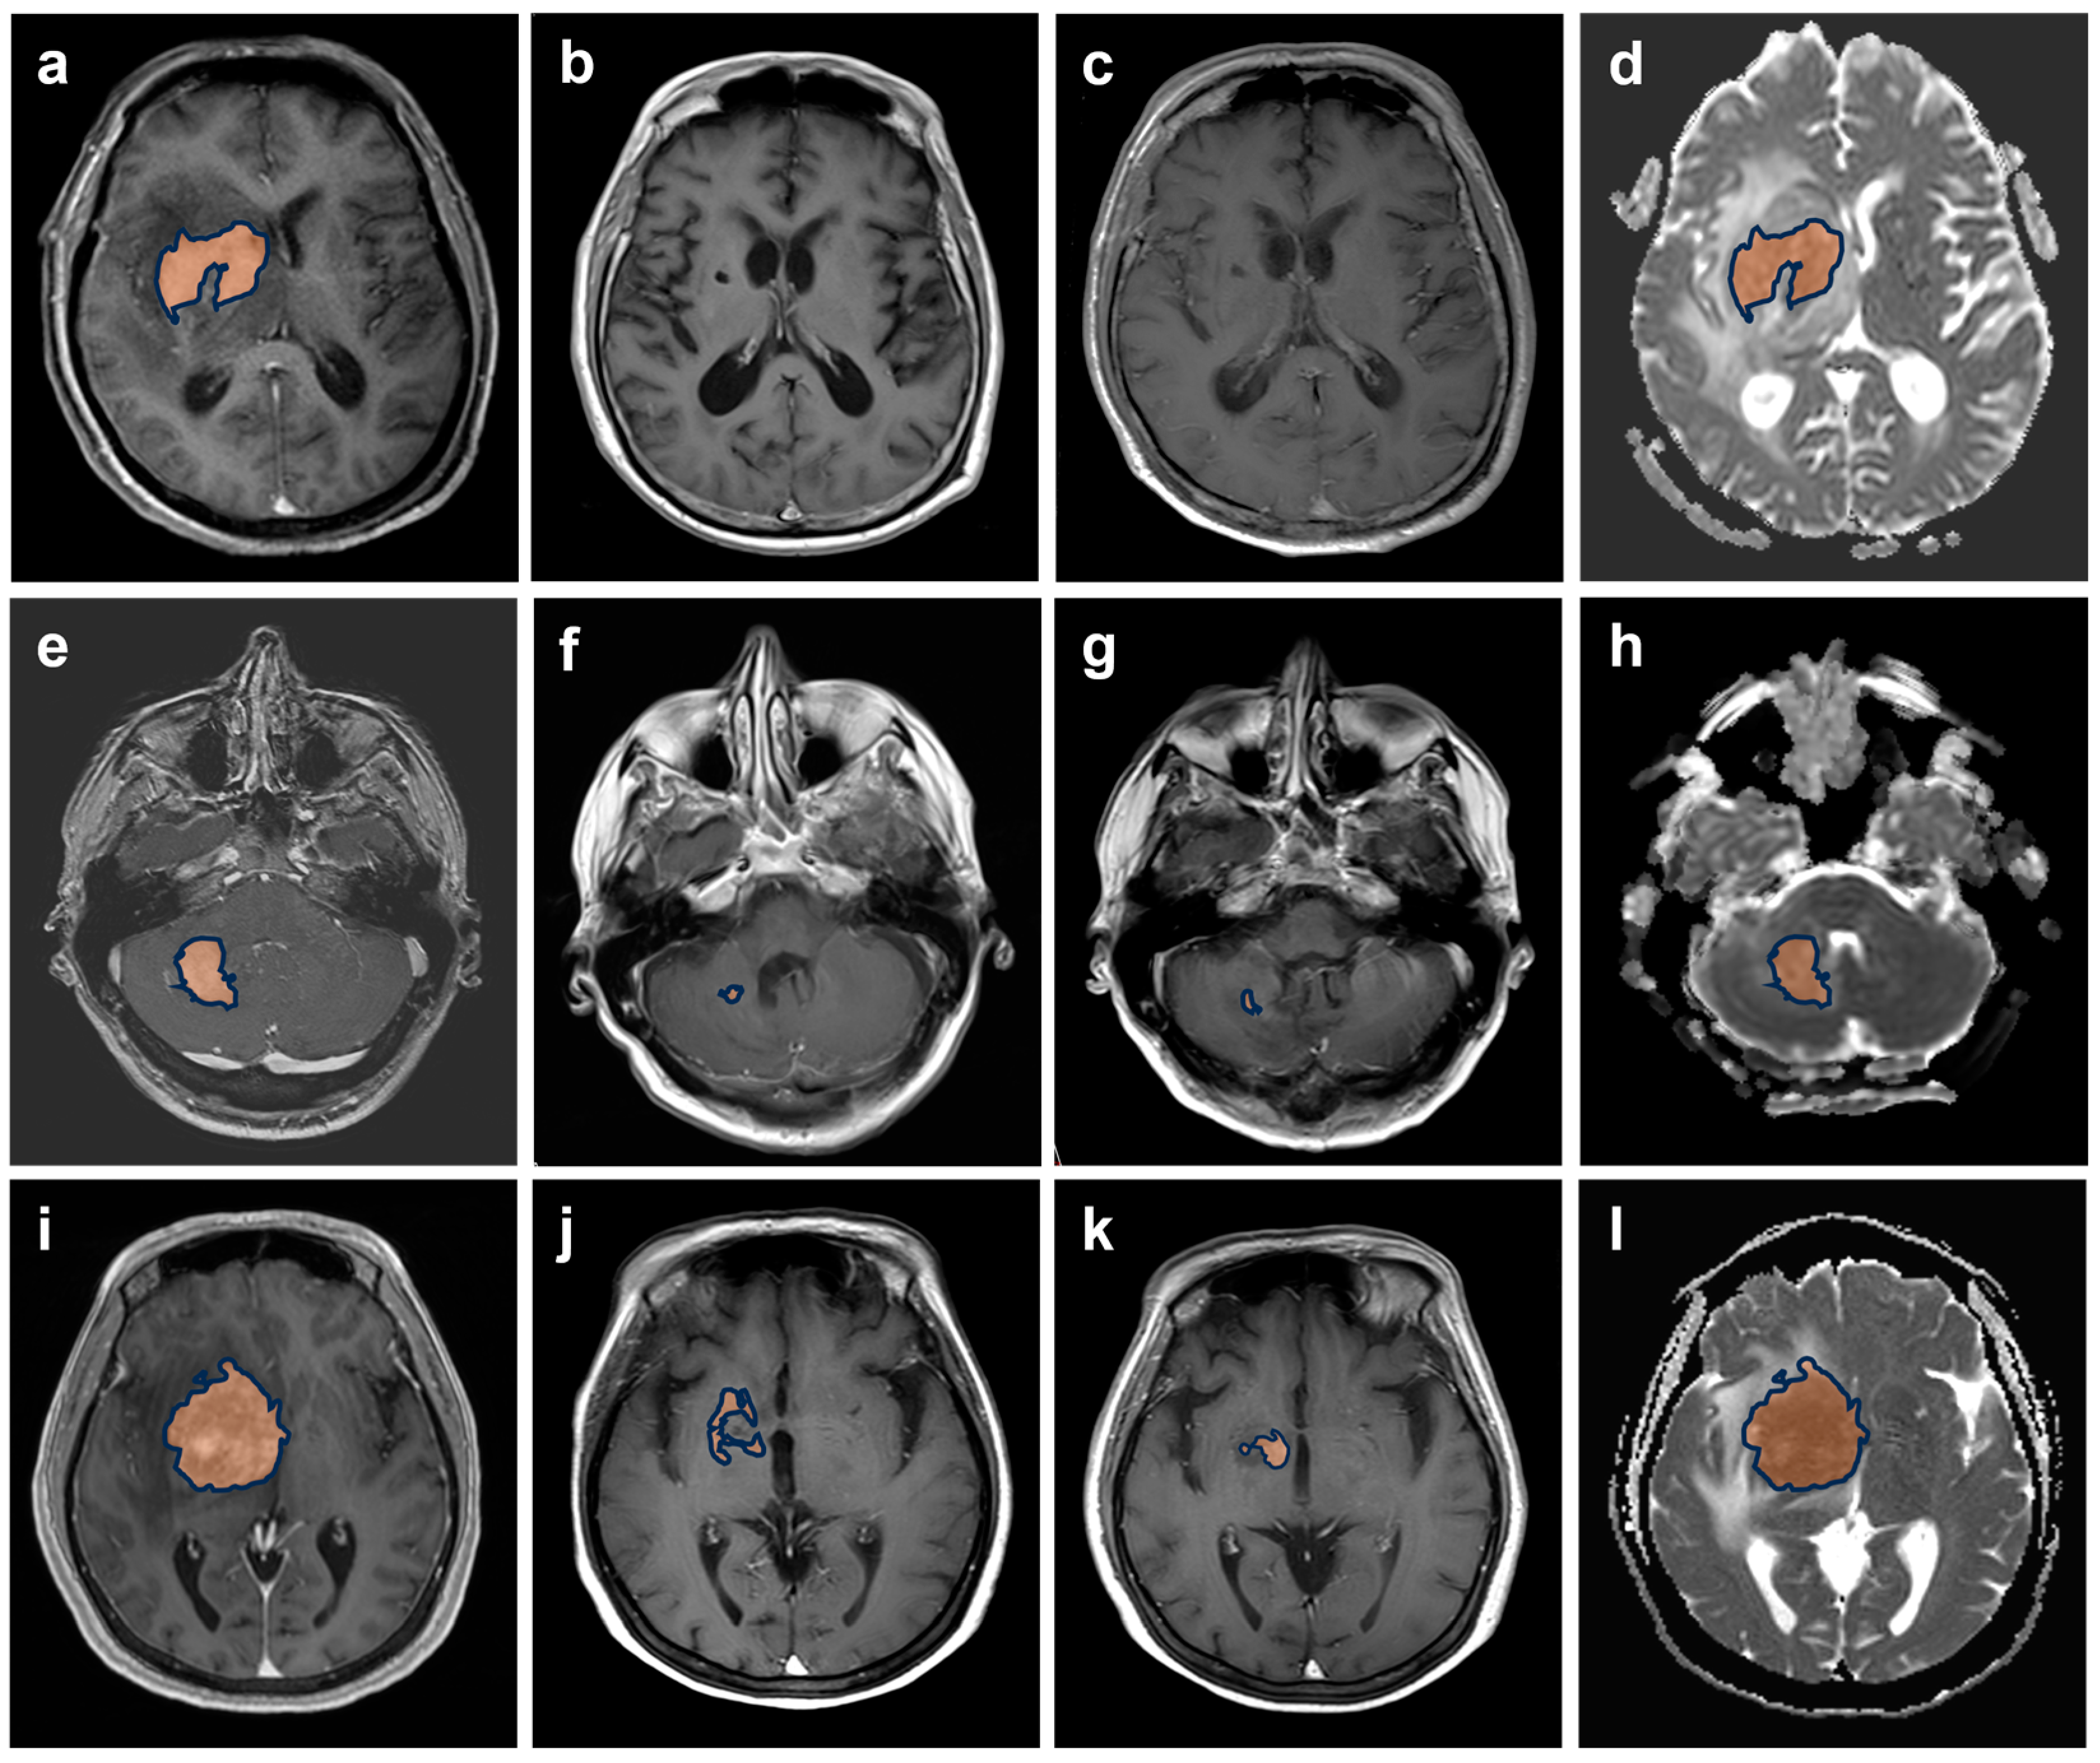

2.2. MRI Acquisition and Post Processing